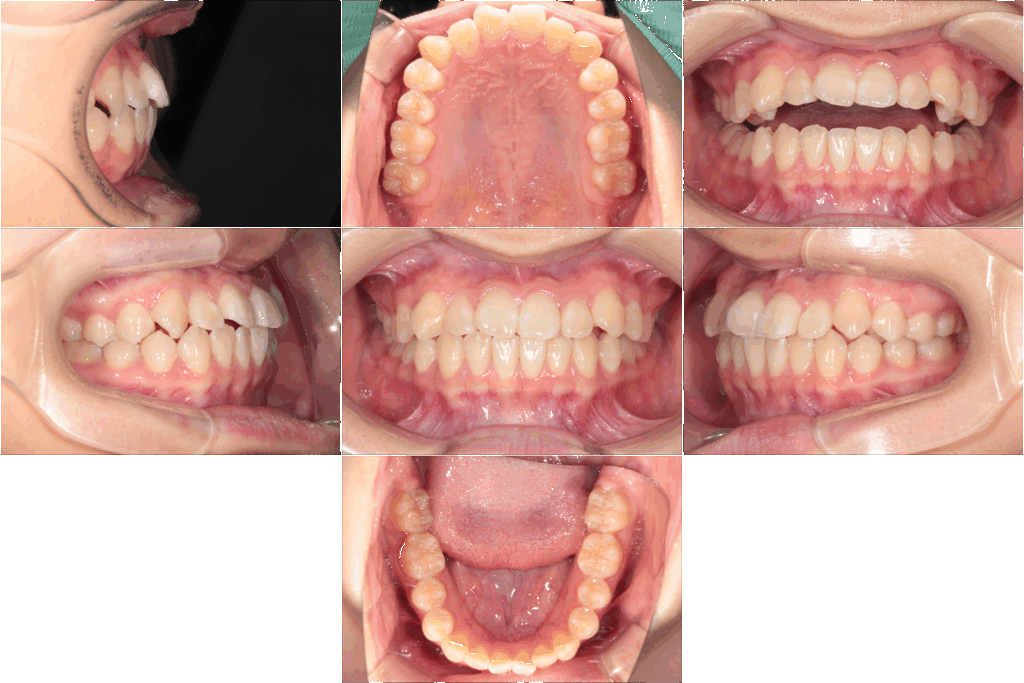

今回の症例は、17歳女子高校生の部分的な矯正治療の紹介です。

主訴は「歯並びのでこぼこ(叢生)」と「上の歯が前に出ていること」。

今回の患者さんは前歯の叢生と上顎前歯の突出が強く、部分的に治療を行うことが適応となりました。

主に前歯のでこぼこが整い、上の歯の突出も穏やかに改善され、自然な歯並びに近づきました。

でこぼこの範囲が前歯中心で、奥歯は比較的良好

上顎前歯の突出は軽度~中等度であった

これらの条件がそろっていたため、マルチブラケット装置による部分矯正で充分に改善が可能でした。